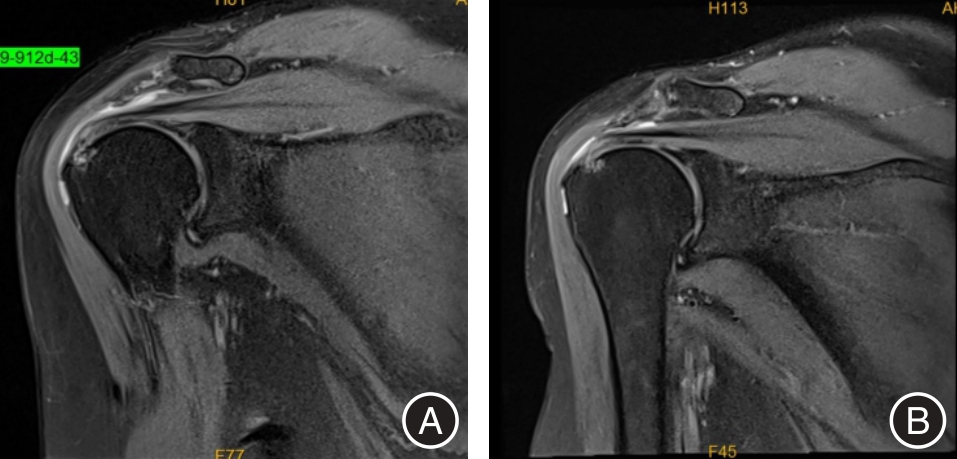

目的 探讨上肢康复机器人(ULRR)联合超声定位体外冲击波(ESW)在轻、中度肩袖损伤治疗中的应用效果。 方法 选取2023年1月至2024年3月安徽医科大学第二附属医院收治的90例轻、中度肩袖损伤患者,随机分A组(基础康复)、B组(基础康复+ESW)、C组(基础康复 + ESW + ULRR)各30例。于治疗前后采用视觉模拟评分(VAS)评估患者肩部疼痛,肩关节位置重现偏差角度评估患者本体感觉,表面肌电图(sEMG)检测患肩三角肌中束、冈上肌、冈下肌积分肌电值(iEMG)和均方根值(RMS),标准量角器测量患肩外旋、外展和前屈主动活动范围(AROM),Constant-Murley肩关节评分(CMS)评估患者肩部整体功能,评估对比3组疗效及满意度。 结果 治疗后,3组患者VAS评分和肩关节位置重现偏差角度显著下降,三角肌中束、冈上肌、冈下肌iEMG和RMS,肩外旋、外展和前屈AROM,以及CMS各项评分(疼痛、日常生活活动、主动活动范围、肌力)显著升高,且C组以上各项指标改善均明显优于A组和B组,差异均有统计学意义(P < 0.05);C组临床有效率和患者满意度明显高于A组和B组,差异均有统计学意义(P < 0.05)。 结论 对轻、中度肩袖损伤患者,上肢康复机器人联合体外冲击波具有更好的治疗效果,能缓解疼痛,还能改善运动功能和本体感觉,提高患者满意度。

Objective To investigate the therapeutic efficacy of the combination of upper limb rehabilitation robots (ULRR) and ultrasound-guided extracorporeal shock wave (ESW) in the treatment of mild to moderate rotator cuff injuries. Methods A total of 90 patients with mild to moderate rotator cuff injuries, who were admitted to the Second Affiliated Hospital of Anhui Medical University between January 2023 and March 2024, were selected and randomly assigned to three groups: Group A (basic rehabilitation), Group B (basic rehabilitation + ESW), and Group C (basic rehabilitation + ESW + ULRR), with 30 patients in each group. Before and after treatment, shoulder pain was assessed using the visual analogue scale (VAS). Proprioception was evaluated based on shoulder joint position reproduction error. The integral electromyography (iEMG) and root mean square (RMS) values of the median tract, supraspinatus, infraspinatus, and deltoid muscles on the affected side were measured using surface electromyography (sEMG). The active range of motion (AROM) for external rotation, abduction, and forward flexion of the affected shoulder was measured using a standard goniometer. Overall shoulder function was evaluated using the Constant-Murley Shoulder Score (CMS). The clinical efficacy rate and patient satisfaction levels were compared among the three groups. Results After treatment, the VAS score and shoulder position reproduction deviation angle in all three groups significantly decreased. Additionally, the iEMG and RMS values of the middle deltoid, supraspinatus, and infraspinatus muscles; the AROM of shoulder external rotation, abduction, and forward flexion; and the CMS scores (including pain, activities of daily living, active range of motion, and muscle strength) all showed significant improvement. Furthermore, the degree of improvement in all evaluated parameters in Group C was significantly greater than that observed in Groups A and B (P < 0.05). Moreover, Group C demonstrated a significantly higher clinical response rate and greater patient satisfaction compared to Groups A and B (P < 0.05). Conclusion For patients with mild to moderate rotator cuff injuries, the integration of an upper limb rehabilitation robot with extracorporeal shock wave therapy demonstrates superior therapeutic outcomes, effectively alleviating pain, enhancing motor function and proprioception, and increasing overall patient satisfaction.